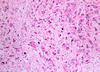

grade this disease

what is found in micro

high grade dysplasia or carcinoma in situ of esophagus

glandular architectural irregularity, nuclear atypia